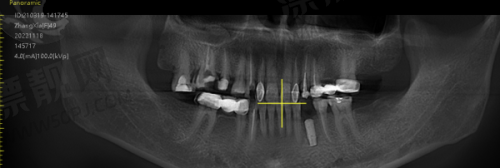

十、罗强口腔连锁种植院:懂你牙齿的城市种牙团队

这家口腔连锁在杭州多个区域设有分院,院长田宗从业十多年,曾进修于上海九院。机构主打精良数字导板进行种植诊断预判,尤其针对多年缺牙及顾虑术后调适的中年层客户建立专属治疗计划。 特色:术前数字模拟种植,全流程可视+追踪。 适合人群:错过黄金修复期、需高质量长期方案者。